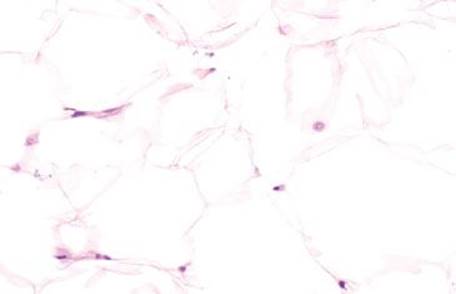

MUCIPHAGES

Azzopardi described muciphages as mucoprotein-containing macrophages in the rectum in 1966.124 The incidence was as high as 50% of rectal biopsies and no correlation with sex, age, or underlying disease was found. Academic interest in muciphages was likely borne out of the 1960s burgeoning understanding of Whipple disease, and a concern that muciphages represented Whipple disease involving the rectum. Today we know muciphages are extraordinarily common with essentially no relation to Whipple disease. A more recent study describes the muciphages as superficially located in the lamina propria and found that up to 19% present as nodules or polyps.2 These experts found a backdrop of increased chronic inflammation and mild fibrosis and suggest muciphages represent nonspecific, resolving injury. Their mucin presumably originates from “clean up” of epithelial damage or turnover (Figs. 4.263–4.269). Detailed studies show the mucin contains neutral, weakly acidic, or strongly acidic mucin with predominantly sialomucin but also a smaller component of sulfated mucin.2 The clinical importance of muciphages is simply to be aware of their benign and nonspecific nature. AFB and GMS special stains are not required upon identification because muciphages are not granulomata and have no association with infections.

Figure 4.266 Muciphages. This low-power image shows the characteristic distribution of muciphages as they decorate the superficial lamina propria.

Figure 4.267 Muciphages. Higher power of previous image. Muciphages are histologically identical to foamy macrophages of any other site.

Figure 4.269 Muciphages. Higher power of previous case shows the muciphages streaming through the superficial lamina propria.